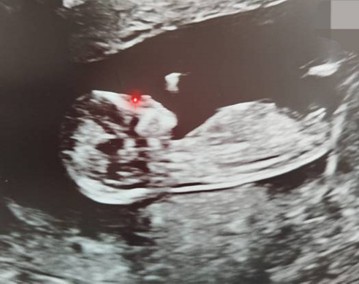

And last, but certainly not least, I feel incredibly lucky that in just a couple of months, my wife and I will be welcoming a brand new little hodler into the world.